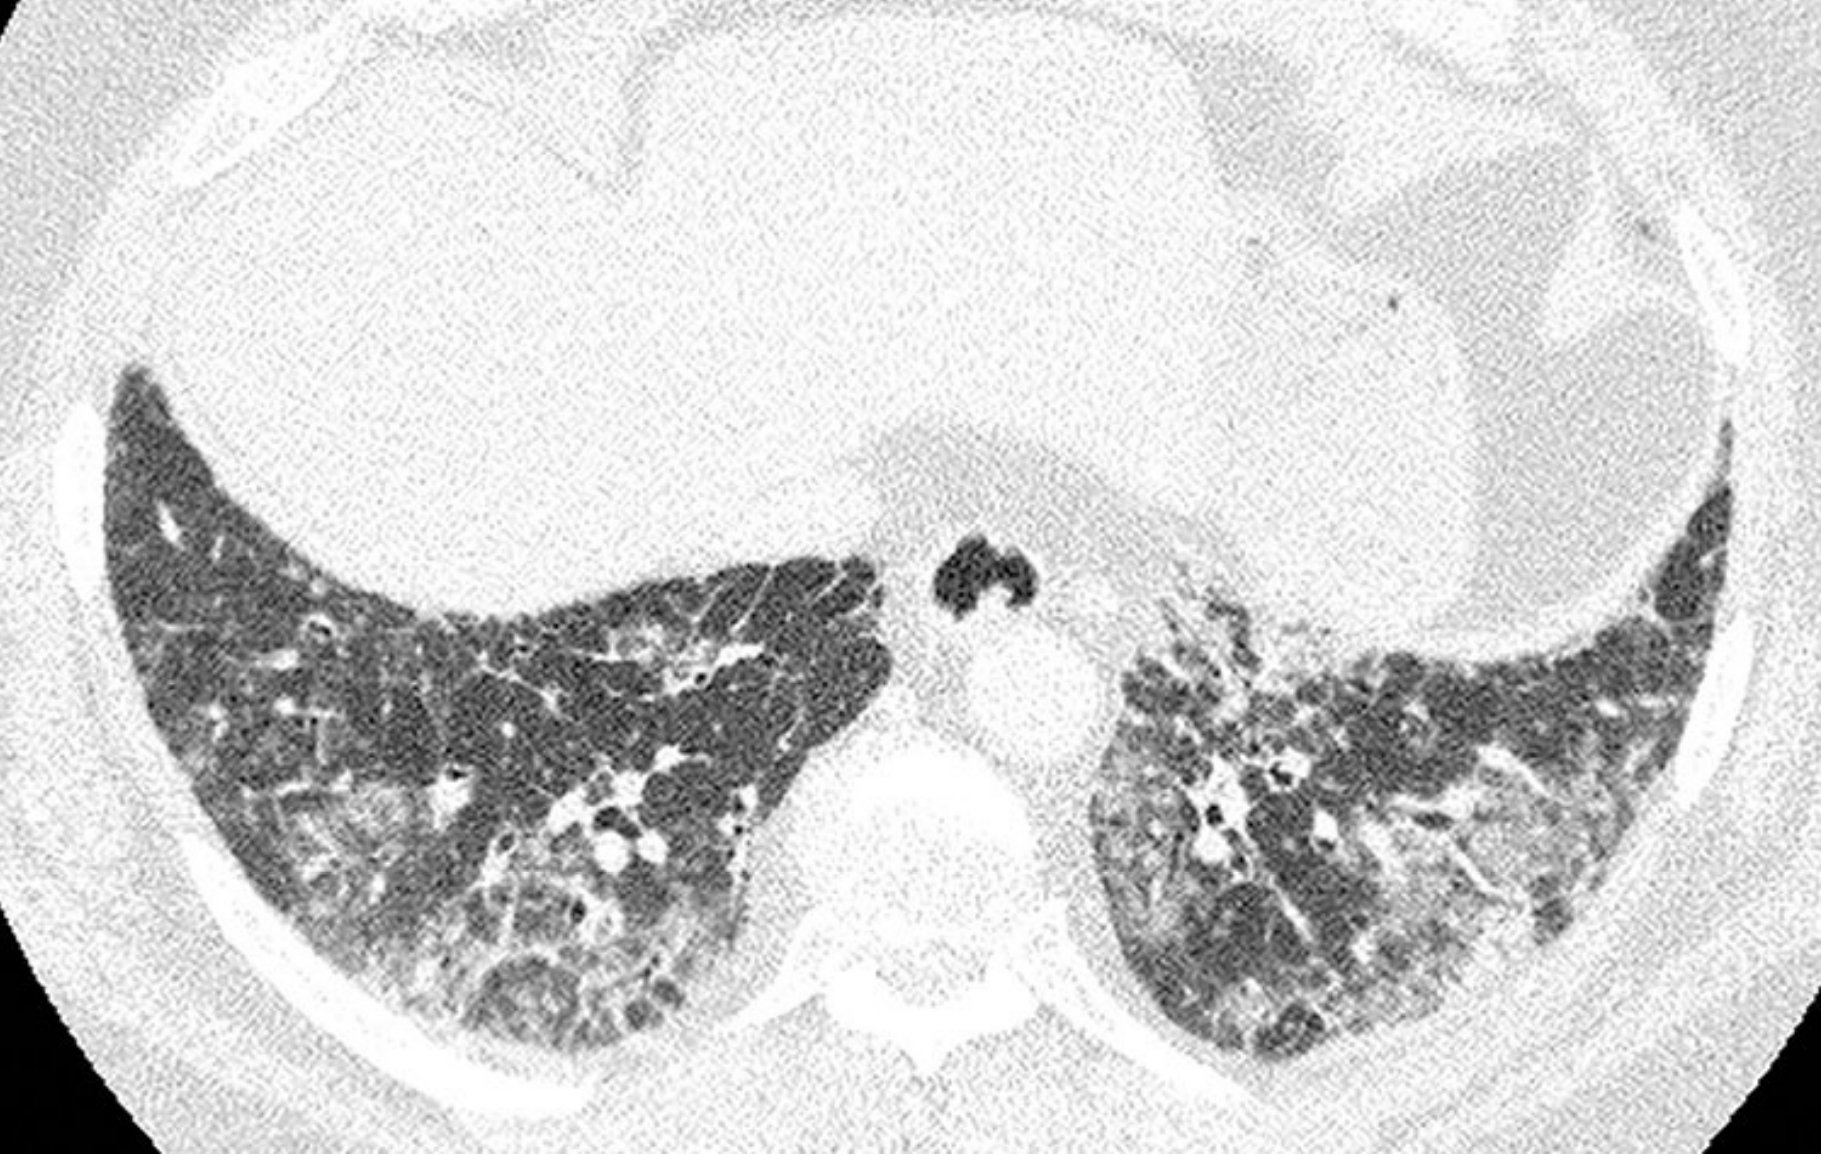

7331218b6857cead2350daf293806044.png

高置信度诊断为普通型间质性肺炎(UIP)的鉴别诊断。

4例UIP的HRCT表现;继发于特发性肺纤维化(A)、结缔组织病(B)、石棉沉着病(C)和药物中毒(D)的UIP, 均可见胸膜下及肺基底分布为主的纤维化伴蜂窝征。当表现为UIP模式时,上述疾病在HRCT上通常无法鉴别。